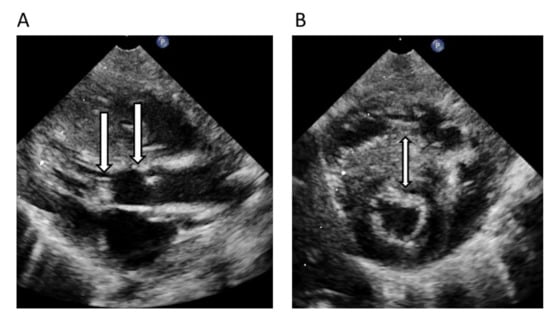

| 6. | II:6 | 11 | F | 2 | HCM/RCM | 3 | 13 | Index patient and brother with SCD as first symptom | PGM1 Chr1(GRCh37):g.64100506G>A, NM_002633.2:c.689G>A, p.G230E | PM2 + PP3 + PS3 Pathogenic/Yes |

| 7. | II:1 | 12 | M | 0 | ASH and AS LVOTO | 2 | 3 | Father with HCM ASH | No result | No result |